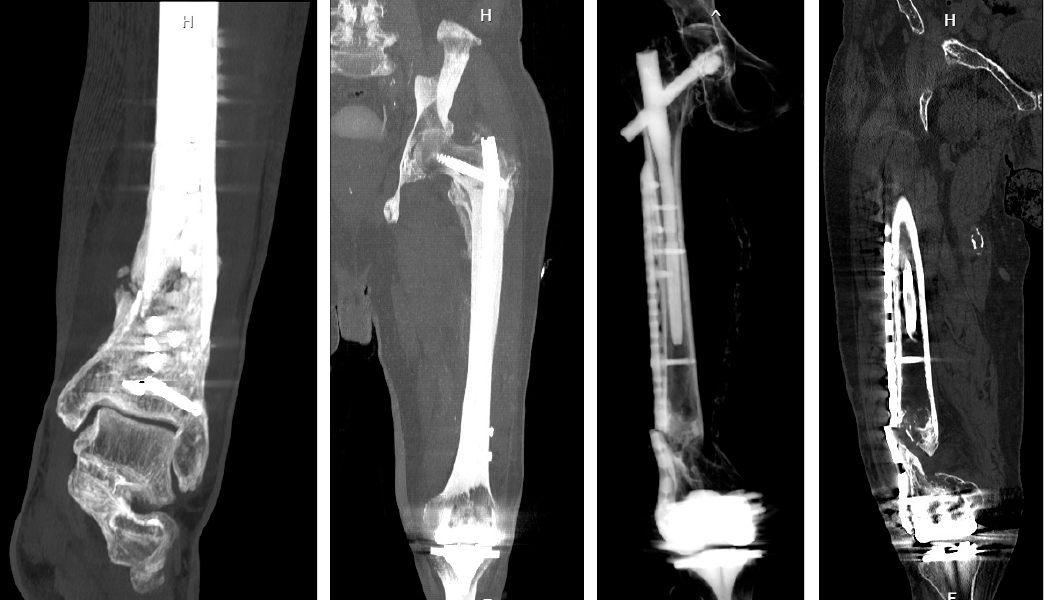

El tratamiento de las pseudoartrosis suele ser quirúrgico, mediante diversas técnicas, como por ejemplo la fijación interna (uso de placas, tornillos o clavos para estabilizar el hueso y favorecer la unión), la limpieza quirúrgica o desbridamiento (eliminar tejido no viable o infectado en casos de pseudoartrosis infectada), la revisión o corrección de alineación o rotación en caso de mala posición de los fragmentos, y el injerto óseo (hueso tomado de otra parte del cuerpo o sustitutivos para promover la formación ósea.